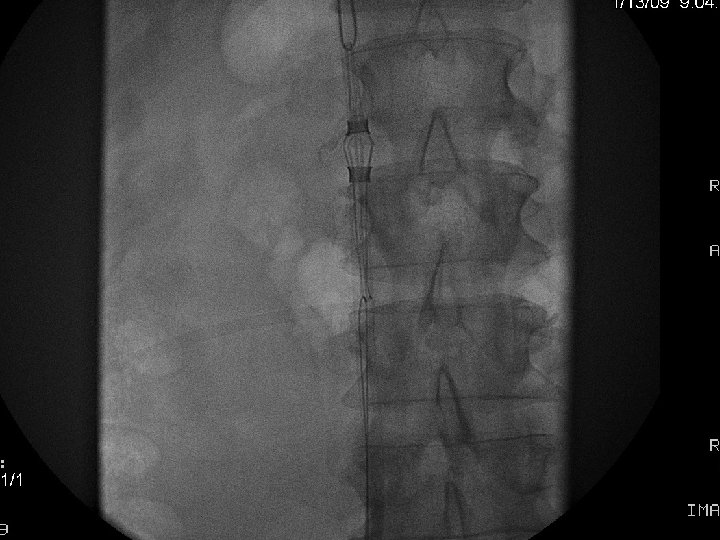

IVC Filter Removal Straight forward and Complex

Equipment Sheaths Directional catheters Directional guidewires Loop snares Grasping devices Baskets

Removal of an “Intravascular Foreign Body” Straight forward Loop snare Grasping device Complex Multiple devices used including angioplasty balloons, bronchoscopy forceps, and the“in situ” snare technique.

Retrieval with a snare and a long sheath or guiding catheter Günther Tulip (Cook) Celect (Cook) Opt Ease (Cordis Endovascular) Option (Angiotech) G 2 X, Eclipse, Meridian (Bard)